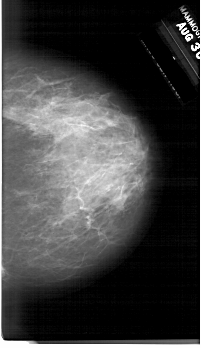

A_1761_1.RIGHT_MLO

RIGHT_MLO LINES 6676 PIXELS_PER_LINE 3886 BITS_PER_PIXEL 12 RESOLUTION 43.5 NON_OVERLAY